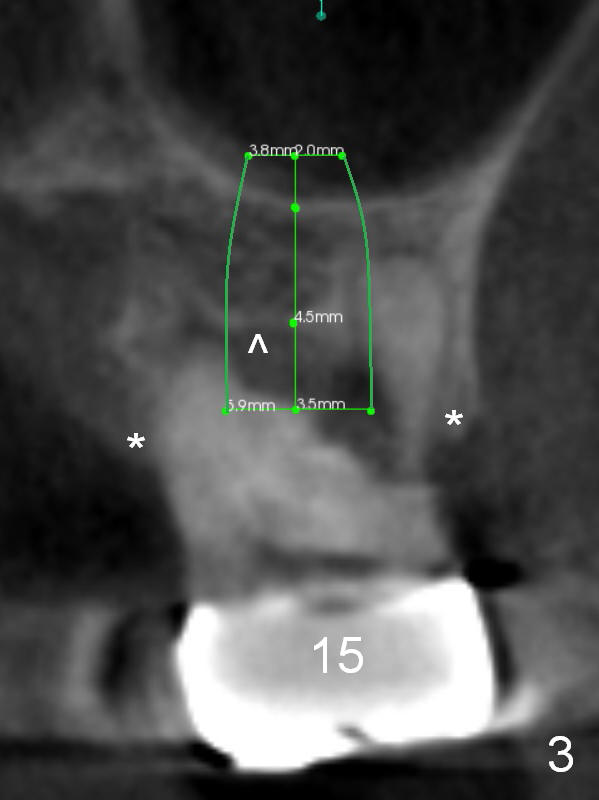

Implant to be Placed at the Level of Crest and Septum

The tooth #15 of a 56-year-old man appears to be non-salvageable due to the large distal cervical caries (Fig.1 (CBCT) C). Immediately after extraction and socket debridement and antibiotic soaking, a 2 mm pilot drill is used for 4 mm, followed by 2.8 and 3.6 mm round burs for 4-6 mm (Fig.1,2 (coronal section)). At #14, the initial depth for 2 mm and 2.8 mm drills is 7 mm. The depth may increase until 9 mm (Fig.1,3). Insert parallel pins after initial osteotomies; check with surgical stent and/or take PA. After placement of allograft/Osteogen, place 4x10 and 6x8 or 10 mm implants at #14 and 15, respectively.